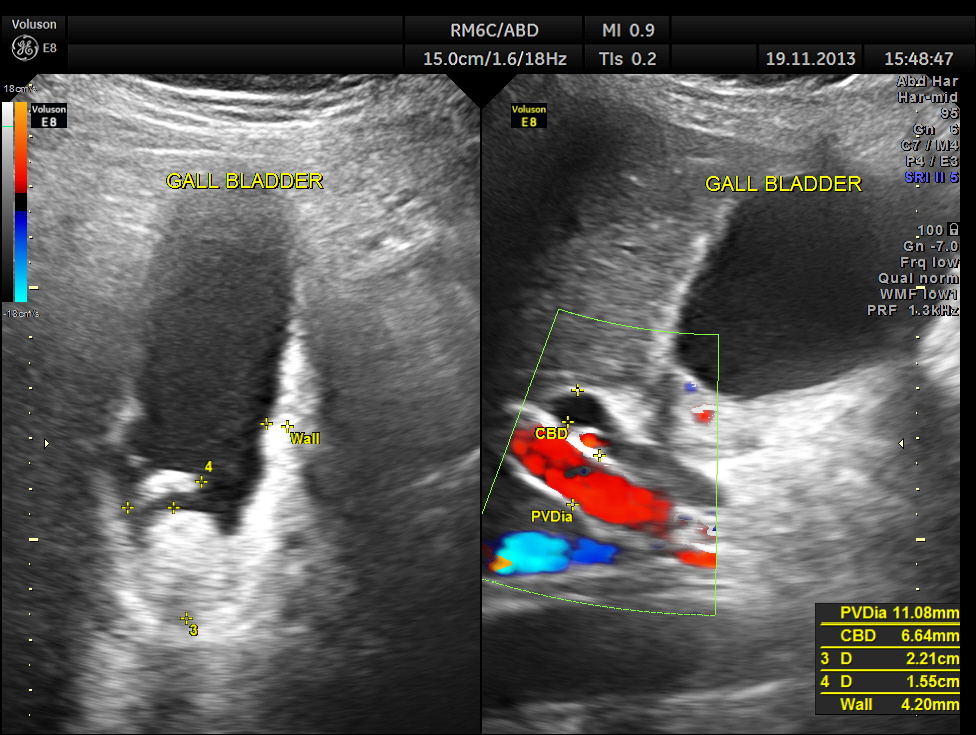

Her abdominal scan revealed a distended gall bladder with two big gallstones and one of them was obstructing the cystic duct.

She had acute cholecystitis with gallstones causing obstruction of the cystic duct.